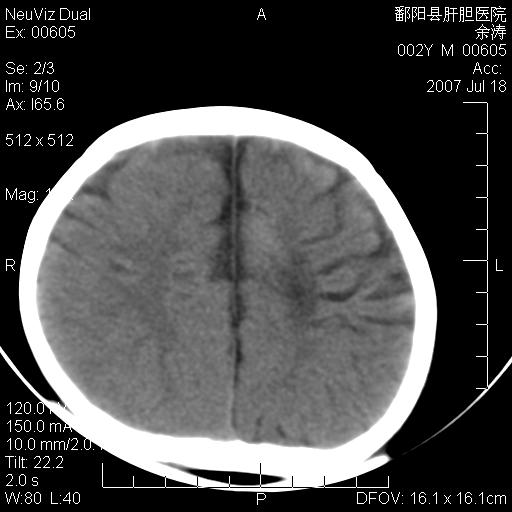

男性 2岁:平时智力障碍。外伤后行颅脑平扫。

左颞叶“萎缩”,可见不规则高密度影,并左侧室扩大,呈负占位效应...支持考虑先天发育异常(血管发育畸形)可能性大,建议结合进一步检查了解。

左颞叶“萎缩”其内可见不规则点条状高密度影,并左侧室扩大,考虑颅面血管瘤病

脑裂畸形;左侧脑脑萎缩;透明隔囊肿;血管畸形?

开唇型脑裂畸形

左侧颞顶叶钙化灶,其内有小片状低密度影 边缘清晰。与之相邻的脑沟增宽增深 ,左侧侧脑室体部牵拉扩大。考虑左颞顶软化灶并局限性脑萎缩。透明隔间腔。

该病人应该还有胼胝体发育不全